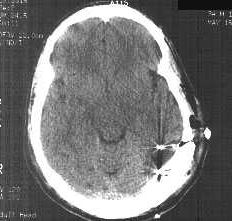

Tomografia rentgenowska CAT (osiowa tomografia komputerowa): używa substancji promieniotwórczych (jodu, baru lub innych) do wzmocnienia kontrastu pomiędzy tętnicami, żyłami lub ukrwionymi narządami, można wykryć guzy, dobrze widoczne różnice płyn CSF, kość, tkanka miękka, ale słabo widoczne tkanki. Wiązka krąży wokół głowy, z licznikiem po drugiej stronie.

Jest to dość bezpieczna technika (dawki promieniowania są niewielkie) i tania, dlatego jest szeroko stosowana w badaniach medycznych, do diagnozy uszkodzeń w wyniku udarów mózgu i chorób różnych organów wewnętrznych.